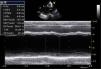

Aos 3 anos de idade apresentou quadro de insuficiência cardíaca congestiva, tendo sido internada em classe funcional New York Heart Association (NHYA) III-IV. A telerradiografia de tórax mostrava marcada cardiomegalia e sinais de congestão pulmonar (Figura 1). O eletrocardiograma (ECG) mostrava dissociação AV com ritmo sinusal e pace ventricular direito com um QRS com a duração de 180ms (Figura 2). O ecocardiograma apresentava VE dilatado [diâmetro telediastólico (VED): 56mm; volume telediastólico (VTD): 90mL] com disfunção sistólica grave (Fej biplano: 20%) por hipocinésia generalizada. O VD tinha boa função sistólica global (Avaliação 2D, TAPSE, Strain). A válvula mitral não apresentava alterações estruturais, mas existia regurgitação funcional moderada a grave. Existia ainda dissincronia AV avaliada por Doppler pulsado espectral do fluxo anterógrado da válvula mitral (em BAV completo) e dissincronia interventricular avaliado por Doppler pulsado espectral do fluxo anterógrado da câmara de saída do VE e VD. A dissiscronia intraventricular estava também presente e era facilmente identificada em 2D/modo M pela presença de movimento septal multifásico designado habitualmente por septal flash. (Figuras 3–5)

Houve uma ligeira melhoria das dimensões do ventrículo esquerdo (VED: 53mm; VTD: 88mL) e melhoria significativa da função sistólica (Fej biplano: 38%). (Figuras 8 e 9). Assistimos também a um redução muito significativa da gravidade da regurgitação mitral que é agora apenas ligeira (Figura 10).